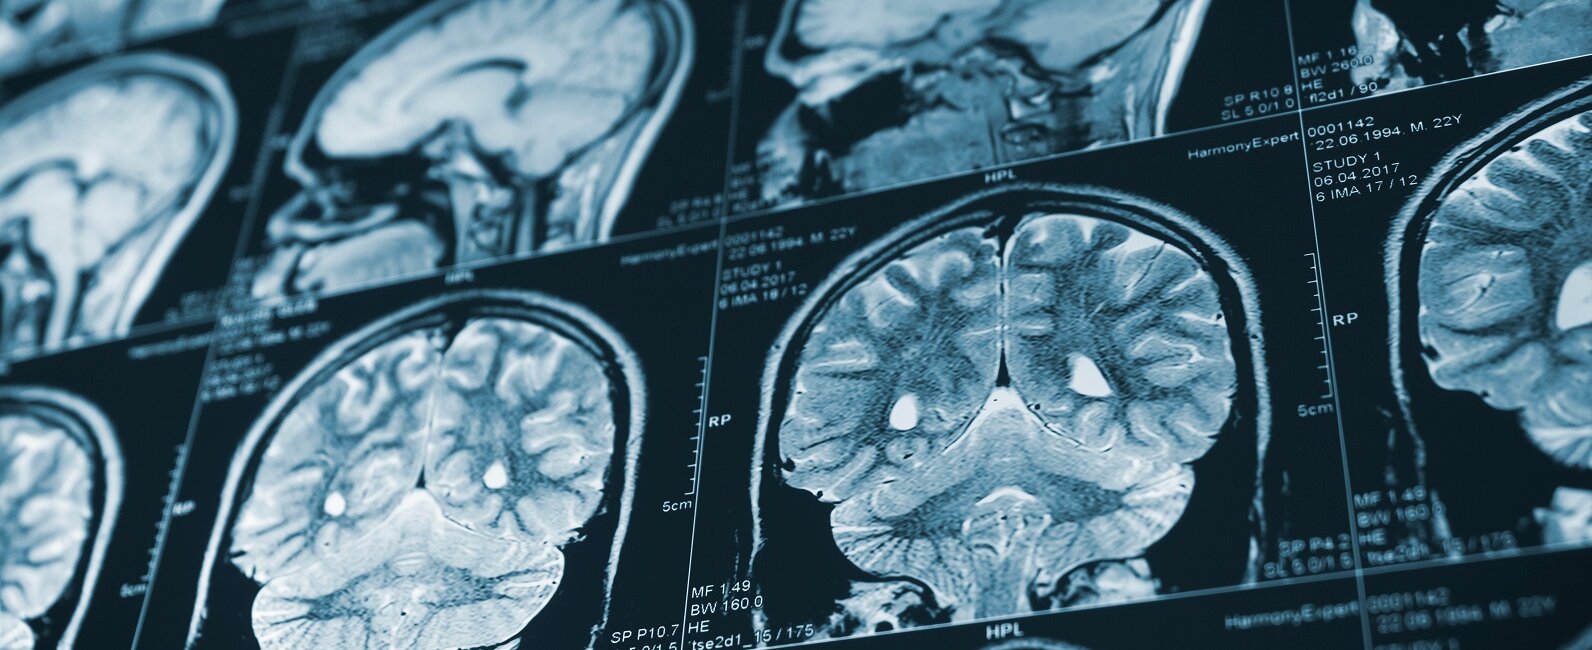

Ha bármelyik problémát okoz számára, ha arca aszimmetrikus, a szavai összefolynak, ha nyelve valamelyik oldalra félreáll vagy ha egyik végtagját nem tudja felemelni, hívjunk segítséget. Koponya CT, Doppler-ultrahang vizsgálat és MRI vizsgálat segít pontosan meghatározni, hogy az agy melyik részért érinti a stroke vagy az agyvérzés, és arról is képet ad, hogy milyen beavatkozásokra, kezelésekre lehet szükség.